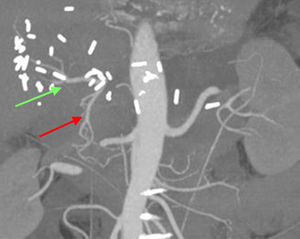

In our patient, the preoperative diagnosis by biopsy allowed us to plan for radical surgery. R0 surgery was performed with resection of the common hepatic artery. This technique, known as the Appleby procedure,10 has been demonstrated to be safe, while increasing survival and ensuring the resectability of locally advanced tumors with vascular invasion. The tumoral obliteration of the common hepatic artery probably favored the vicarious hepatic vascularization through the gastroduodenal artery, as demonstrated by CT angiogram 2 weeks after the procedure (Fig. 2).